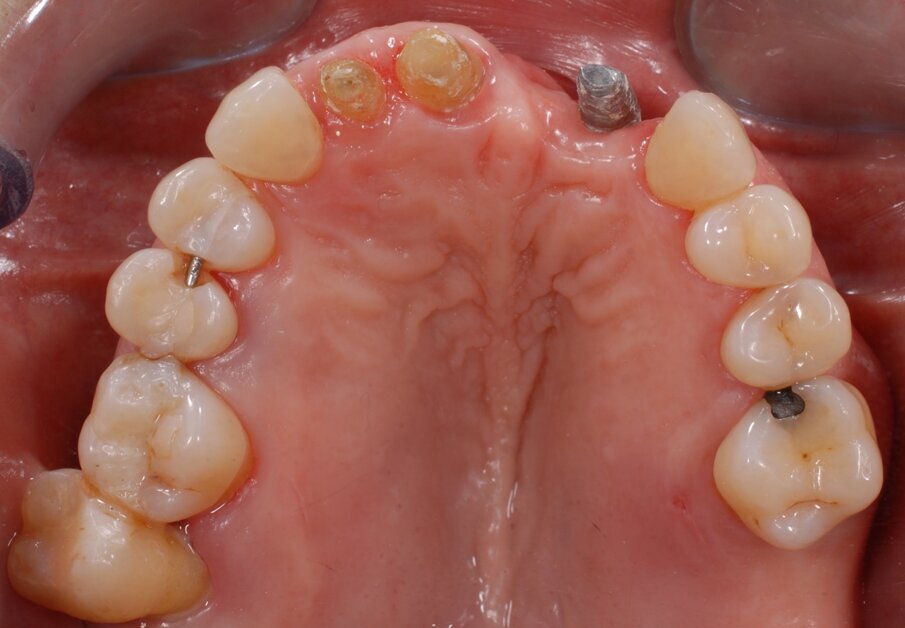

In questo articolo presentiamo un caso clinico che dimostra come il posizionamento improprio di un impianto può rendere impossibile la riabilitazione protesica, che richiede una nuova pianificazione chirurgica e riabilitativa per ottenere l’estetica desiderata. La paziente si presenta alla nostra osservazione con una riabilitazione protesica incongrua, con flangia in resina, a supporto dentale ed implantare, con la presenza di un impianto in posizione 2.1 vestibolarizzato e con l’emergenza nel fornice, in mucosa alveolare. Dalla valutazione della Tac si evince la posizione errata dell’impianto e la perdita consistente in senso trasversale della compagine ossea (Figg. 1, 2). Pertanto si opta per il seguente piano di trattamento che prevede: rimozione dell’impianto e preparazione protesica dell’elemento 2.3, confezionamento di un primo provvisorio a supporto dentale che servirà a guidare la guarigione dei tessuti (Figg. 3-7). A distanza di 4 mesi si procede a un innesto epitelio connettivale libero con prelievo dal palato per compensare il gap dei tessuti molli in senso trasversale, quindi viene ribasato il provvisorio in modo tale da favorire la guarigione dei tessuti (Figg. 8-11). A 9 mesi dalla maturazione dei tessuti si procede alla finalizzazione protesica fissa a supporto dentale (Figg. 12-14).

Fig. 1 - Situazione clinica iniziale.

Fig. 4 - Visione occlusale dopo rimozione del manufatto protesico si noti la posizione errata dell’impianto.